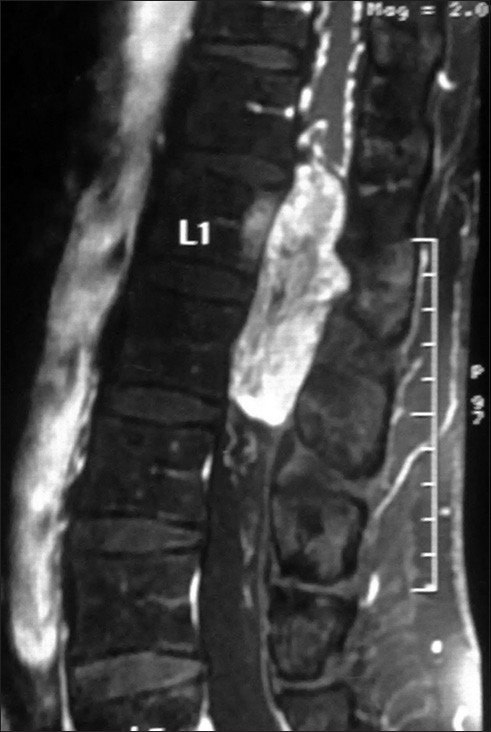

Our patient, a 50-year-old man, a known case of hypertension, on two antihypertensive drugs, was admitted with history of progressively increasing weakness with stiffness and numbness in both lower limbs since 9 months. The patient also had history of urinary and fecal incontinence. Neurological evaluation revealed spastic paraparesis with power 3/5 (MRC grading system) and decreased sensation below L1 dermatome bilaterally. Perianal sensation and anal tone were decreased. Magnetic resonance imaging of the lumbosacral spinal segment, before and after gadolinium administration, demonstrated a lobulated lesion extending from lower border of D12 to L2 vertebra level, intimately related to conus medullaris. It was isointense on T1W images [Figure 1], heterogeneous on T2W images [Figure 2]a and b and showed intense postcontrast enhancement [Figure 3]. Significant scalloping of posterior margin of vertebral bodies and their posterior elements were seen [Figure 4]. There was extension of the lesion into bilateral L1-2 neural foramina. The patient was planned for surgery keeping the possibility of ependymoma. D12 to L2 laminectomy with subtotal excision of the tumor was done. The tumor was hyper-vascular. The rostral part of the tumor was adherent to conus and was inseparable, so left behind. During surgery, blood pressure increased considerably on few occasions, but was controlled. On postoperative day 1 the patient had flushing all over the body, specially over the face and chest region, palpitation, dysphagia, and uncontrolled blood pressure. The patient was shifted to the intensive care unit where his blood pressure was not controlled in spite of giving three antihypertensive drugs. His blood and urine were sent for all necessary investigation including the serum catecholamine level. On the same day the patient collapsed and expired after an episode of hematemesis. The histopathological examination revealed a diagnosis of paraganglioma. Typical "Zellballen nests" of neoplastic cells were present surrounded by a delicate fibro-vascular stroma. [Figure 5]a and b The cells possessed granular eosinophilic cytoplasm and demonstrated nuclear pleomorphism. Immunohistochemical testing showed a positive reaction for chromogranin and S100 protein. Serum noradrenaline level was 2951 pg/ml (normal 100-450 pg/ml) with normal adrenaline level. | Figure 4: X‑ray of the Dorso‑lumbar region showing significant scalloping of posterior margin of L1 vertebral bodies and their posterior elements

The role of MRI in the diagnosis and treatment of this condition is paramount, owing to the abundance of anatomical information it provides, although a correct diagnosis may pose some problems. On T1-weighted images, the lesion usually has an isointense appearance, whereas it is hyper-intense on T2-weighted sequences with enhancement after Gadolinium administration. These features are common to other intradural lesions, such as schwannomas, ependymomas, meningiomas, metastatic tumors. In the diagnostic work-up of paraganglioma, two observations may be helpful in differentiation form other lesions (1) a defect in the serpiginous structure between the conus and the lesion, suggesting dilatation of the serpentine vessels, which is uncommon in schwannomas and ependymomas [Figure 2]a and [Figure 3]. (2) A hypointense appearance of the tumor rim on T2-weighted sequences, suggesting paramagnetic effects caused by hemosiderin, which is typical of vascular tumors, since hemosiderin discoloration is a sign of prior hemorrhage. [12],[13],[14]